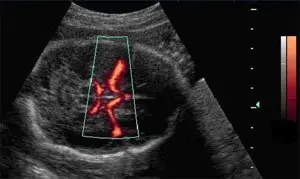

附圖是威利氏環( circle of Willis )的超音波影像,此影像屬於那一種超音波掃描?

- B-mode 背景影像:影像背景為灰階的 2D 超音波,呈現胎兒頭部(或經顱超音波)的橫切面。

- 彩色取樣框(Color box):在腦部中央(大腦基底)放置了一個梯形的彩色取樣框,框內顯示出威利氏環(circle of Willis)及其主要分支血管的血流分佈。

- 血流與色階條(Color bar)特徵:

- 觀察影像右側的色階條,為單一色系的漸層變化(從暗紅色到明亮的黃白色),且沒有零基線(zero baseline)。

- 取樣框內的血管皆呈現單一色系(亮橘紅色),並未區分血流是朝向或遠離探頭。這代表該影像顯示的是都卜勒訊號的「強度(amplitude/power)」,而非「頻率偏移(速度與方向)」。

- A. color Doppler(彩色都卜勒):彩色都卜勒利用紅、藍雙色圖譜(BART 原則:Blue Away, Red Towards)來顯示血流的方向與平均速度。其色階條中間會有黑色的零基線。由於本圖右側的色階條與血流皆為單一色系且無方向性,故可排除此選項。

- **B. power